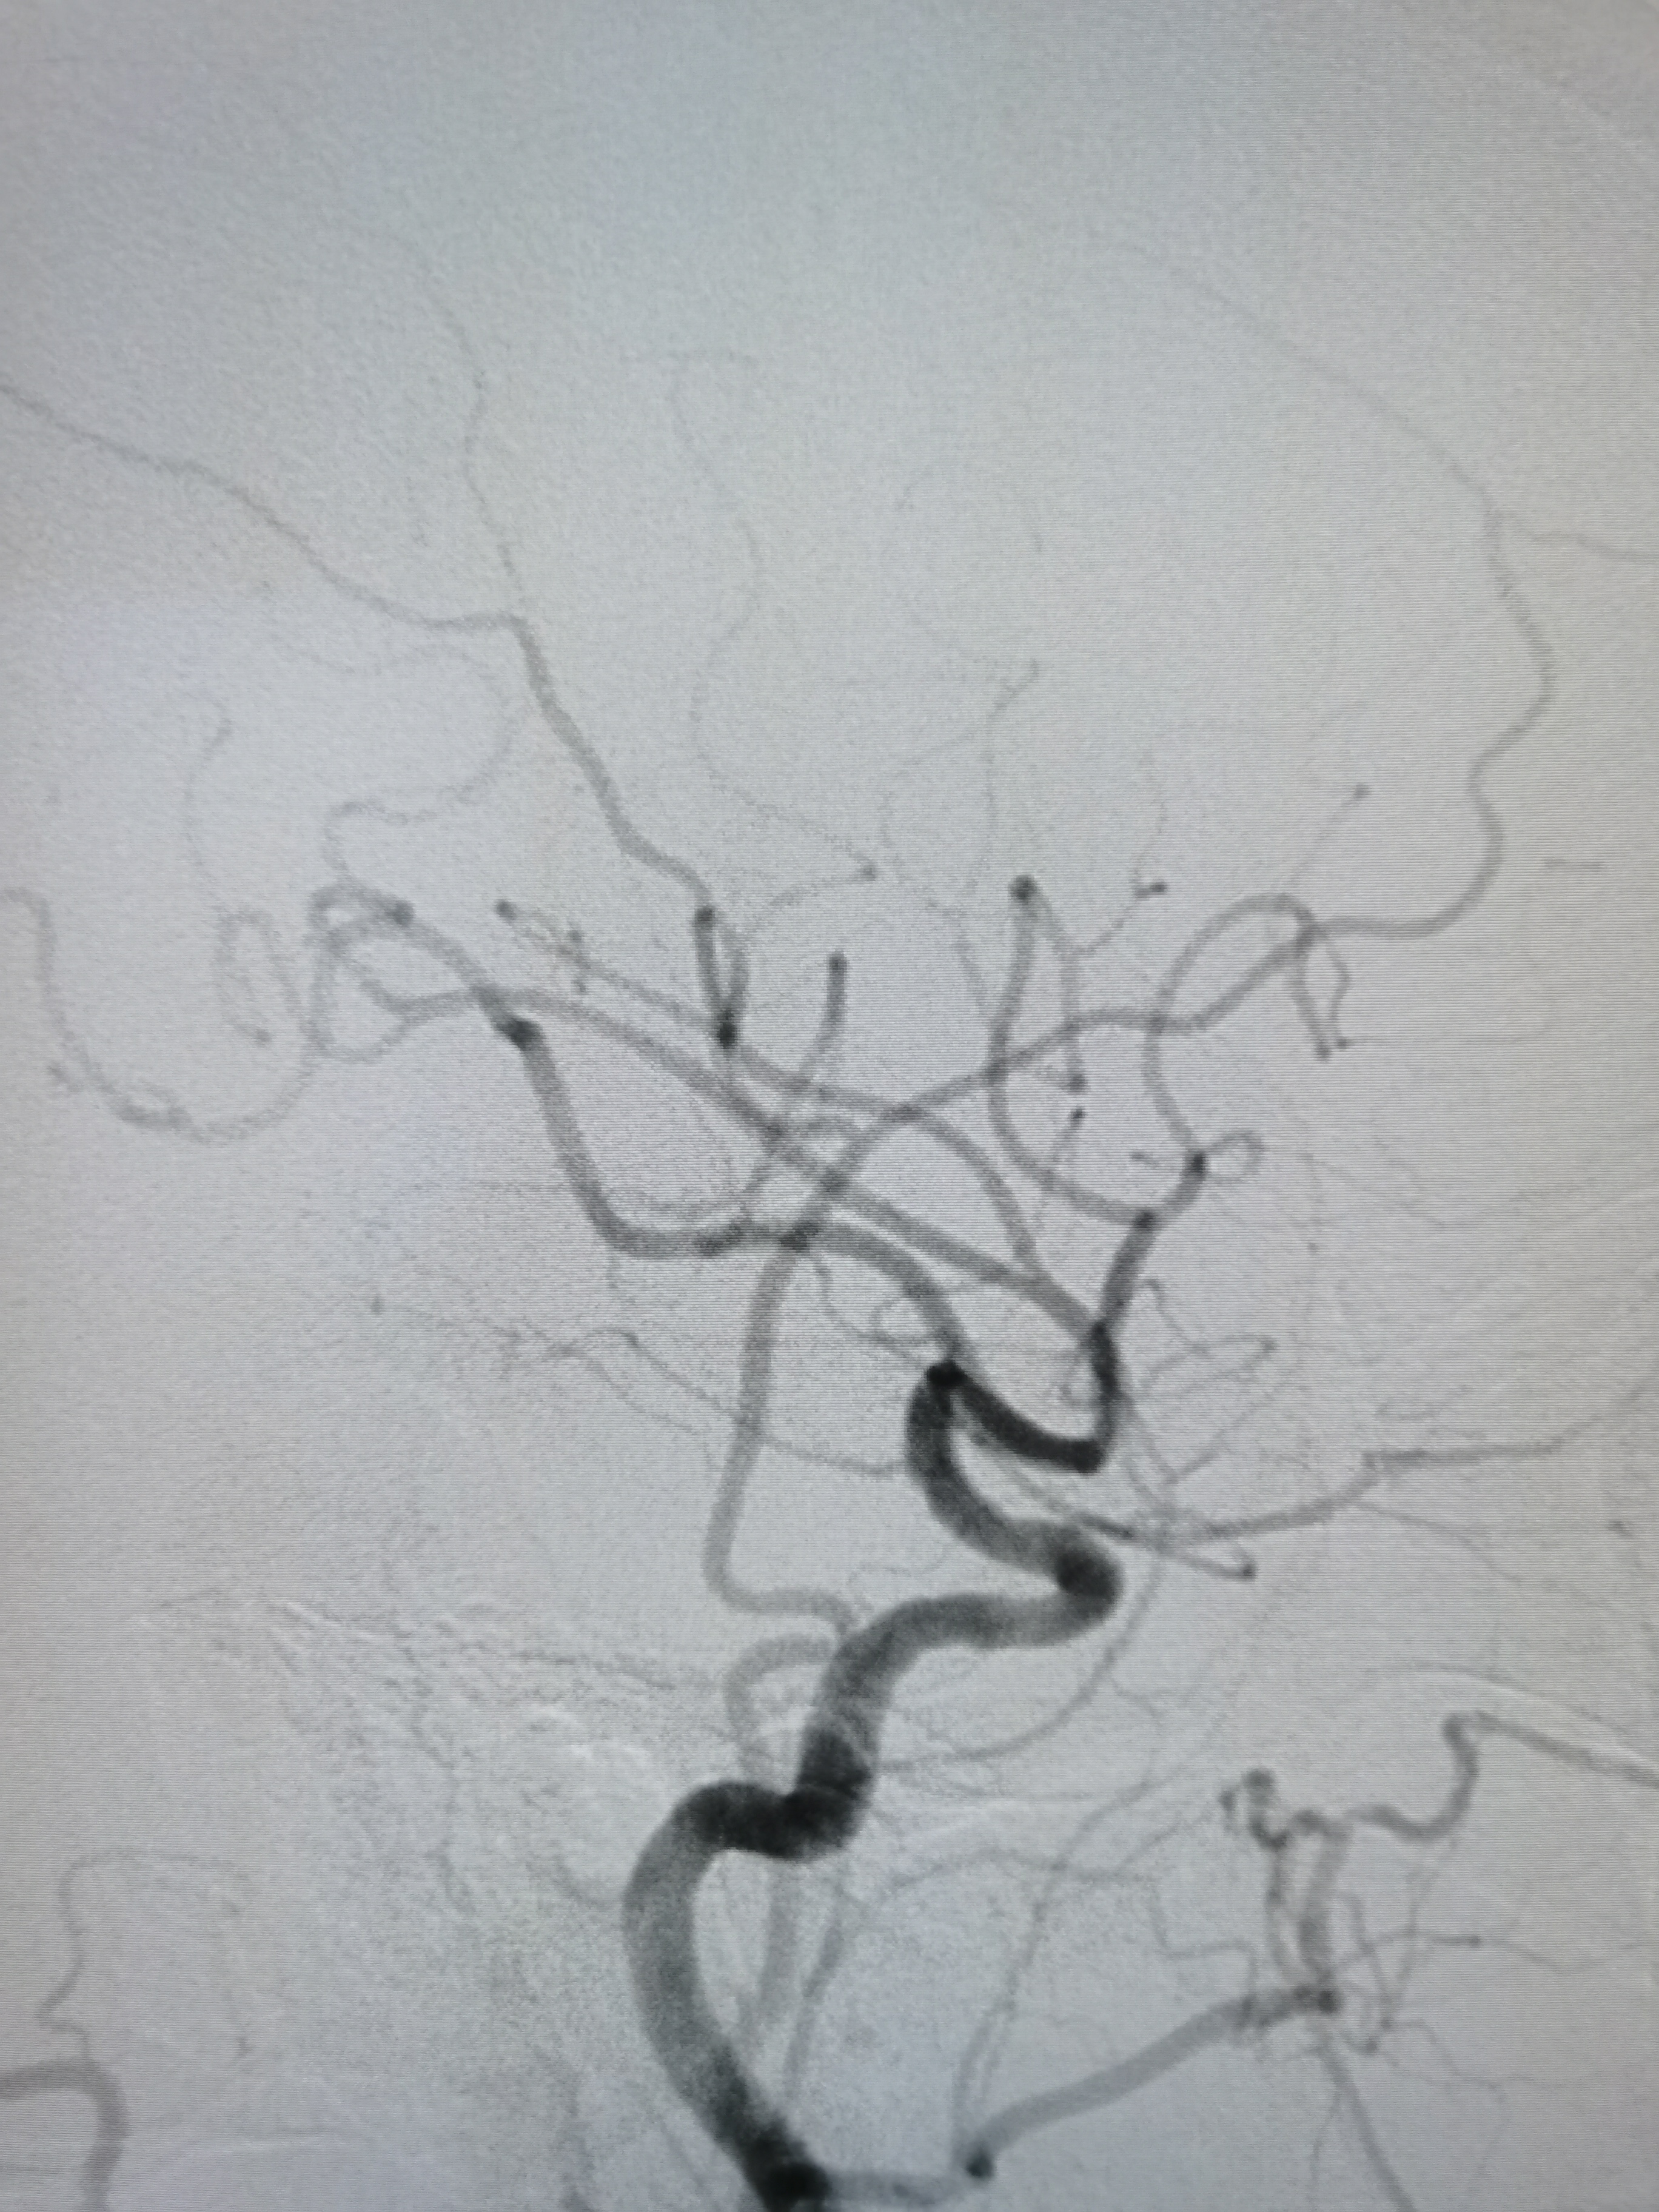

颅内段显影可。

右侧孤立大脑中动脉,M1轻度狭窄。